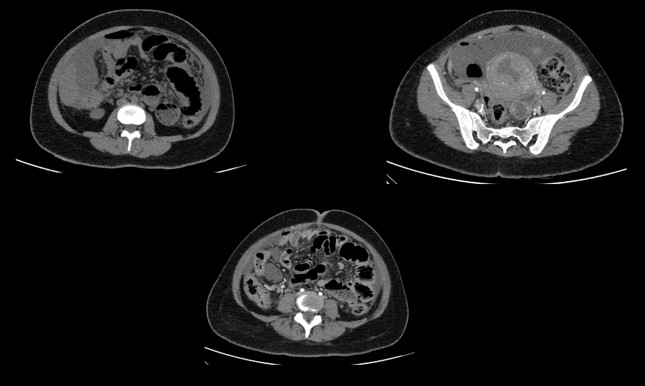

CECT ABDOMEN AND PELVIS - DAY 1

• A. Mild pneumoperitoneum. Few heterogeneously enhancing fibroids seen. Tubular hypodense area in left adnexa - likely pyosalpinx Diffuse greater omental fat stranding and peritoneal thickening - suggestive of peritonitis.

• B. Tubular hypodense area in left adnexa - likely pyosalpinx. Subserosal fibroid in upper corpus.Few loculated fluid pockets with air foci are seen in the pouch of douglas